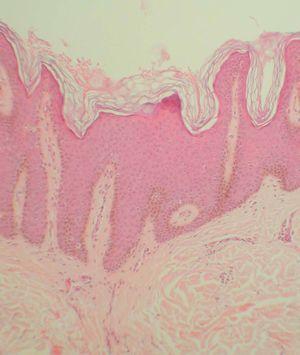

Una radiografía simple de tórax practicada de urgencias no mostró ninguna anormalidad, así como un hemograma y una bioquímica básica (incluyendo ionograma, función renal, glucosa y transaminasas). Se realizaron varias biopsias cutáneas, incluyendo muestras de las lesiones papilomatosas más grandes. En la figura 3 se puede observar la imagen histopatológica de una de las placas.

Fig. 3.--Imagen histopatológica de una de las placas (espalda). (Hematoxilina-eosina, x100.)

Las imágenes de todas las biopsias eran superponibles. Se apreciaba una hiperqueratosis ortoqueratósica «en cesta de mimbre», junto con acantosis y papilomatosis. Las papilas presentaban de manera característica un mismo tamaño, y la epidermis suprayacente a éstas se encontraba levemente adelgazada. Las células de la capa basal mostraban cierta hiperpigmentación. En algunos cortes era posible observar focos de disqueratosis acantolítica. En la dermis superficial se apreciaba un leve infiltrado inflamatorio inespecífico, y en algunos puntos un elevado número de melanófagos. Una tinción con ácido peryódico de Schiff (PAS) no mostró hallazgos adicionales.

La histopatología es idéntica en todos los tipos de acantosis nigricans. Se observa hiperqueratosis, papilomatosis y acantosis moderada. De forma característica, las proyecciones de la dermis hacia la epidermis suelen ser de la misma longitud, con una epidermis suprayacente adelgazada. Puede haber una ligera hiperpigmentación de la capa basal, aunque el color oscuro de las lesiones suele ser debido a la hiperqueratosis existente en las lesiones de mayor evolución12.